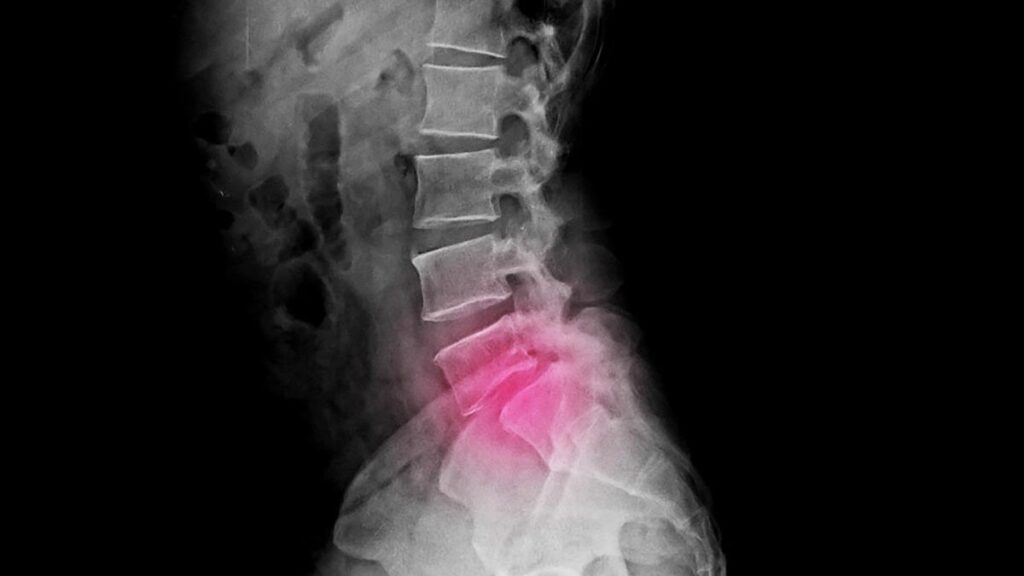

A espondilolistese é classificada de várias maneiras, com base na etiologia, no grau de deslizamento e em parâmetros radiográficos e clínicos. As principais classificações incluem:

Classificação de Meyerding:

O médico ortopedista Henry William Meyerding, da Mayo Clinic (Minnesota/USA), nasceu em 05 de setembro de 1884 em St. Paul/Minnesota, e em 1938 idealizou um sistema de classificação de espondilolistese baseado na porcentagem de deslizamento de uma vértebra em relação à outra. Esta classificação tem como base radiografias laterais da coluna em posição neutra. Os graus são definidos da seguinte forma:

• Grau I: 0% a 25% de deslizamento.

• Grau II: 25% a 50% de deslizamento.

• Grau III: 50% a 75% de deslizamento.

• Grau IV: 75% a 100% de deslizamento.

• Grau V: Deslizamento maior que 100% (espondiloptose)

Os graus I e II são considerados de baixo grau, enquanto os graus III a V são de alto grau.